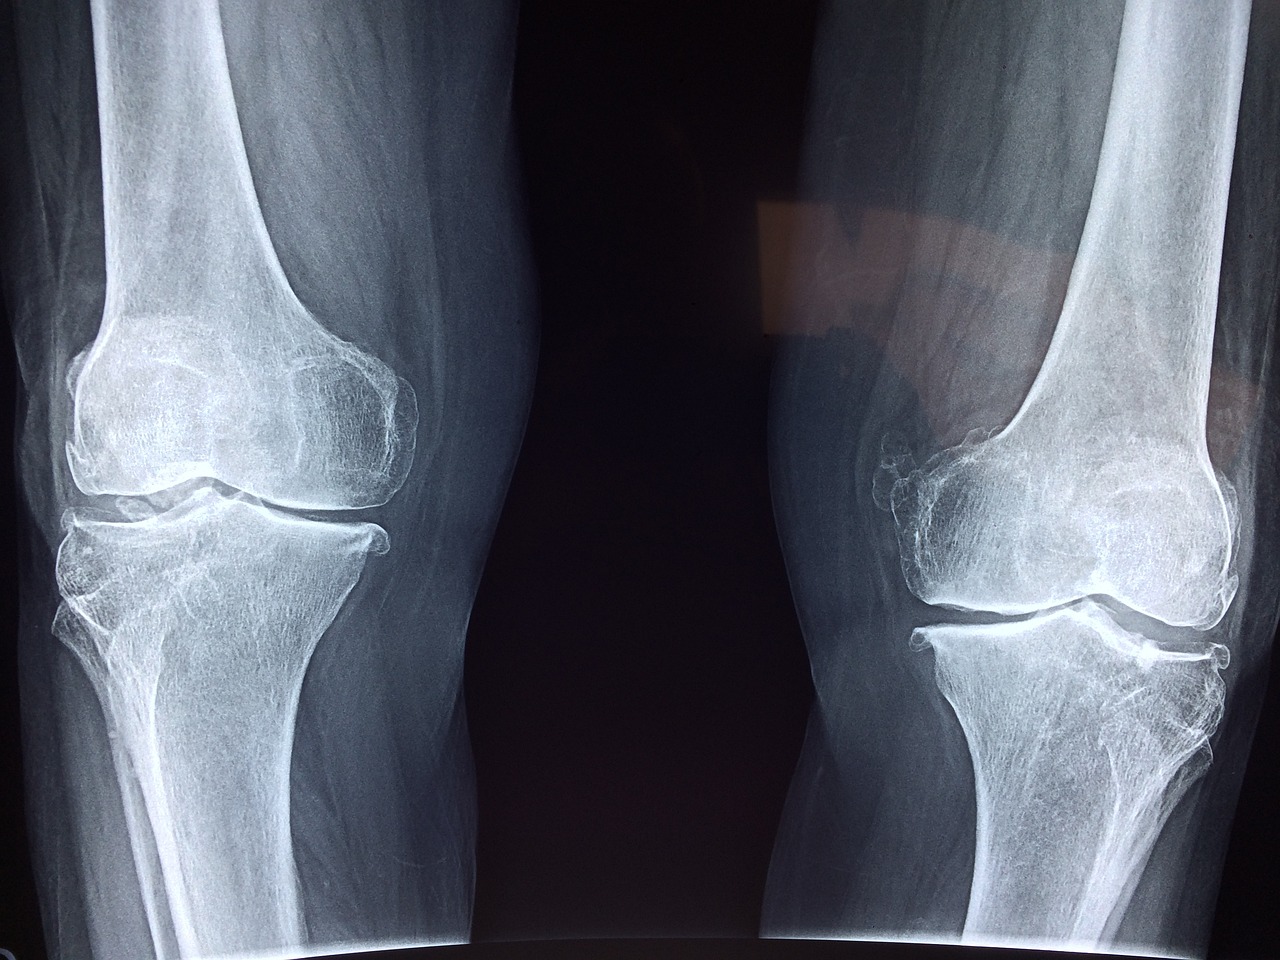

퇴행성 관절염은 말 그대로 노화로 인해 생기는 병으로 뼈의 관절면을 감싸고 있는 관절의 연골이 마모되어 생기는 병입니다. 관절 주변에 활액막에 염증이 생기고 이 염증이 치료되지않을 경우 통증이 심해지면서 물이 차기도 합니다.